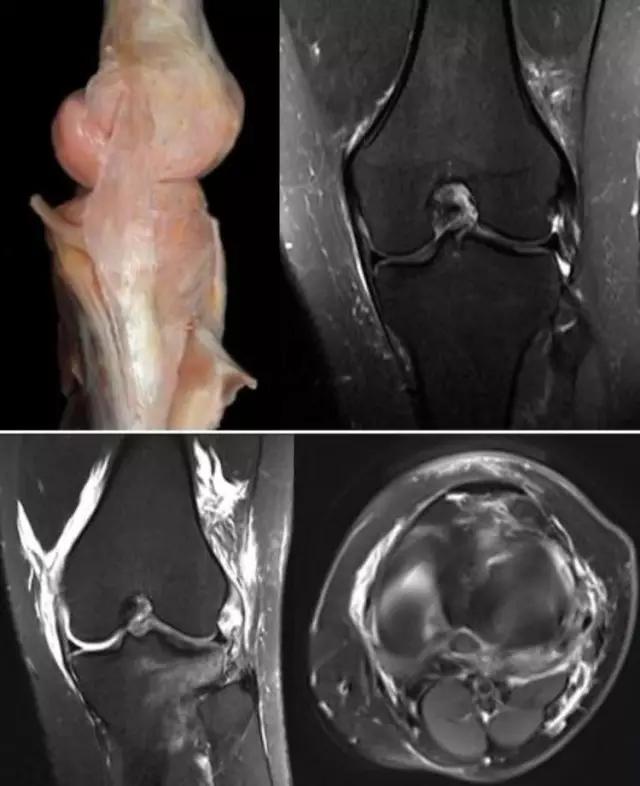

地中海贫血与白血病均为血液系统的问题,主要表现在骨髓,疾病的发病机理有别,MRI表现也不相同;我们可能不是很熟悉这些疾病,也能够从MRI发现区别。图1:正常膝关节 图2:地中海贫血 图3:白血病

我们可能都不熟悉T1、T2,怎么办?当我们发现有问题后,利用照片上图像的对比,推测病变的可能也是一种诊断方法。病例:黄XX,女,39岁,左膝关节反复交锁1年。图1:肿物信号与骨信号一样图2:肿物信号与骨信号一样图3:肿物信号与骨信号不一样 肿物应该与骨相关,但不是骨性,推断:膝关节滑膜软骨瘤。手术后得到证实。

膝关节结核为侵袭性病变,会破坏膝关节的滑膜、软骨、骨等,所形成的寒性脓疡会顺着策划间隙流注,与其他疾病的表现不同。 病例:李XX,女,56岁,右膝关节疼痛逐渐加重8个月。手术及病理证实为膝关节结核。